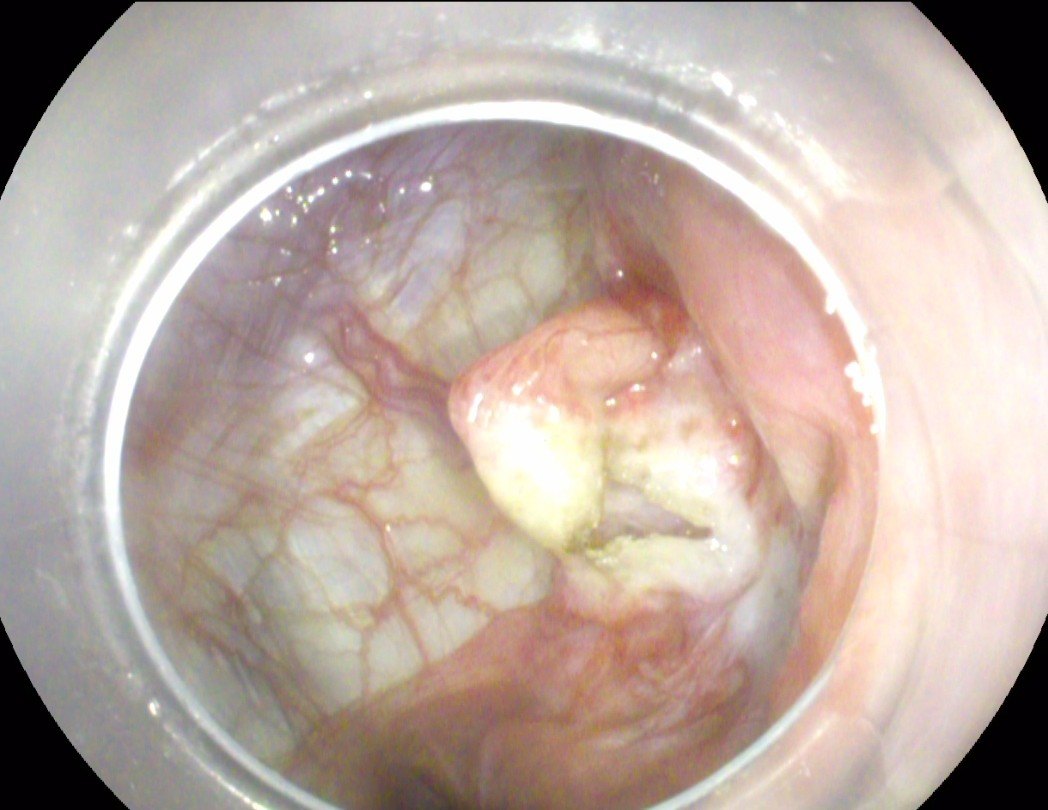

经口胃镜下肝囊肿开窗术 - 好大夫在线

图片尺寸1045x809